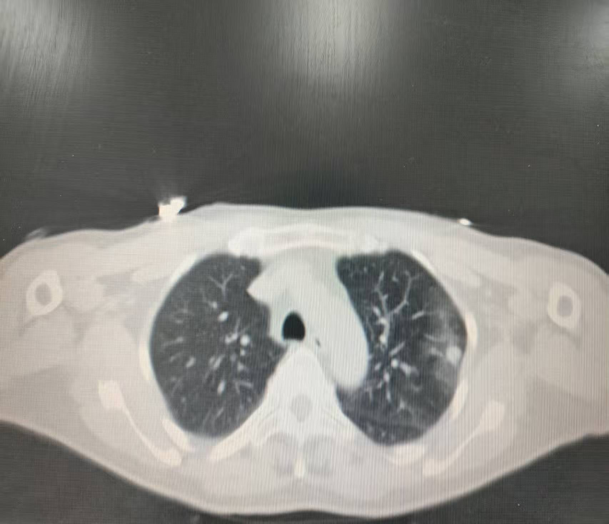

左肺上叶转移瘤